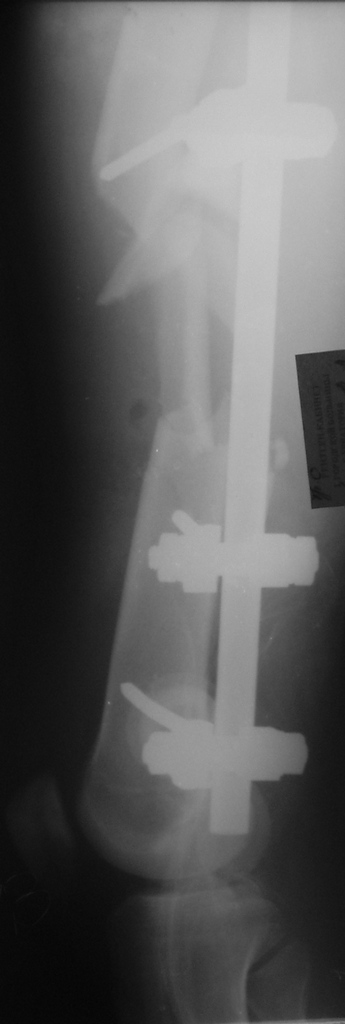

Вчера сделали снимки - положение отломков и осколков вот такое. На перевязке: из раны небольшое кол-во сгустков крови с примесью гноя , хотя бедро спокойное, гипертермии ни локальной ни общей нет. Вопрос: как быть дальше? открывать рану, "чистить" ее, наладить ее перфузию АС, АБ? что делать с осколками, попробовать перекрыть область перелома с фиксацией основных отломков аппаратом. Или осколки убрать и состыковать основные отломки с жутким укорочением и большими проблемами при зашивании раны?

Имя     : левое бедро боковая проекция.JPG

Имя     : левое бедро прямая проекция.JPG